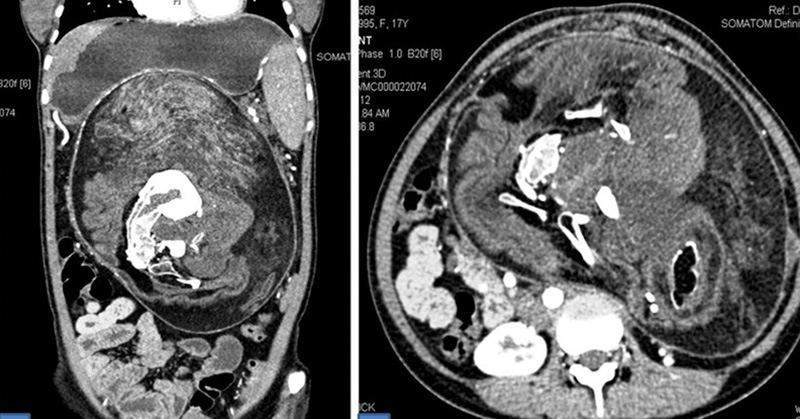

Joven vivió 17 años con un ‘gemelo’ dentro de su cuerpo sin saberlo

Los especialistas señalan que se trata de un fenómeno que ocurre en uno de cada millón de nacimientos del que existen menos de 200 casos registrados en la literatura médica.